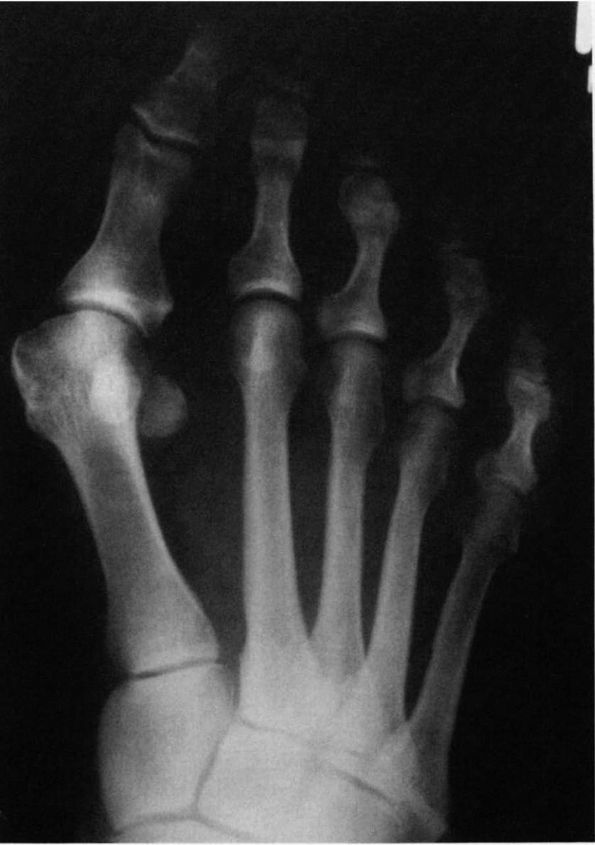

![]() |

FIGURE 21-2.

Radiograph of a hallux valgus deformity. Note the lateral deviation of the proximal phalanx on the metatarsal head, the medial deviation of the metatarsal head, and subluxation of the sesamoids. |